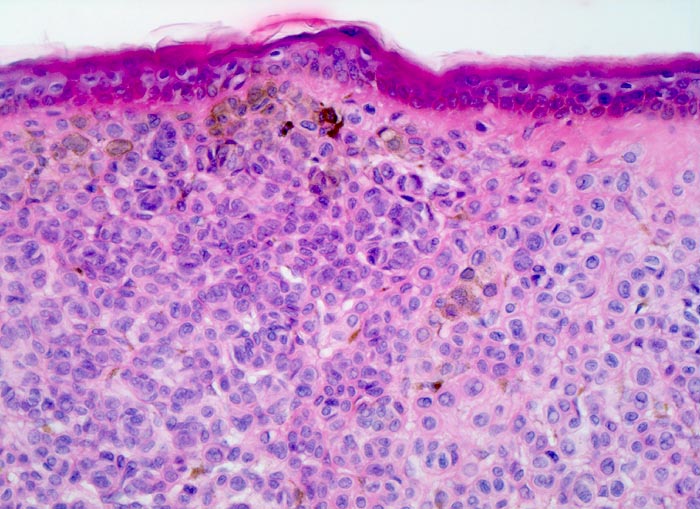

• Symmetrischer leicht exophytischer Tumor.

• Die Tumorzellen bilden Nester in der Epidermis und in der Dermis (=dermoepidermaler bzw. compound Naevus).

• Oberflächliche Tumorzellen enthalten teilweise körniges braunes Melaninpigment.

• Angrenzend an die pigmentierten Zellnester sind Melanophagen erkennbar, deren Zytplasma mit Melaningranula angefüllt sind.

• Die oberflächlichen Naevuszellen zeigen reichlich helles, teils pigmentiertes Zytoplasma und helle ovale Kerne mit kleinen, deutlich erkennbaren Nukleolen. Zur Tiefe hin werden die Naevuszellen kleiner, haben weniger Zytoplasma und dunkle kleine Kerne ohne gut erkennbaren Nucleolus. Die Zellnester werden zur Tiefe hin ebenfalls kleiner (=Ausreifung).

• Keine Mitosen, keine Zellatypien.